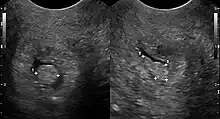

Cervical polyps can be seen during a pelvic examination as cherry-red or greyish-white projections from the cervical canal.[2] Diagnosis can be confirmed by a cervical biopsy which will reveal the nature of the cells present.[4]

Structure

Cervical polyps are finger-like growths, generally less than 1 cm in diameter.[1] They are generally bright red in colour, with a spongy texture.[7] They may be attached to the cervix by a stalk (pedunculated) and occasionally prolapse into the vagina where they can be mistaken for endometrial polyps or submucosal fibroids.[5]